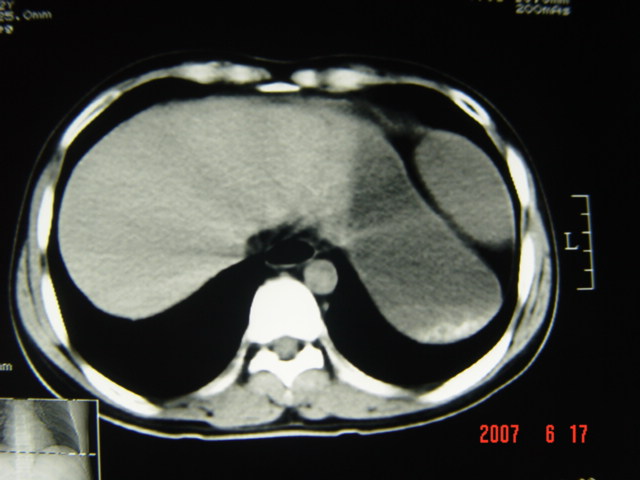

[br][br]以下是引用lkc8963在2007-6-17 13:32:00的发言:[br]完全支持邓主任意见:降/乙交界部占位性病变伴不全梗阻.做个增强或者be可能更好.